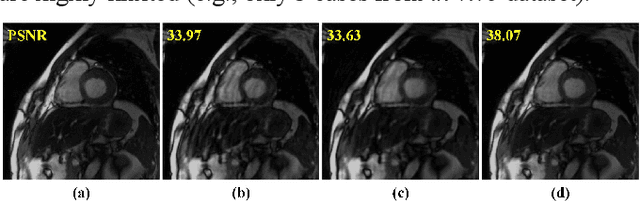

Abstract:Dynamic magnetic resonance imaging (MRI) plays an indispensable role in cardiac diagnosis. To enable fast imaging, the k-space data can be undersampled but the image reconstruction poses a great challenge of high-dimensional processing. This challenge leads to necessitate extensive training data in many deep learning reconstruction methods. This work proposes a novel and efficient approach, leveraging a dimension-reduced separable learning scheme that excels even with highly limited training data. We further integrate it with spatiotemporal priors to develop a Deep Separable Spatiotemporal Learning network (DeepSSL), which unrolls an iteration process of a reconstruction model with both temporal low-rankness and spatial sparsity. Intermediate outputs are visualized to provide insights into the network's behavior and enhance its interpretability. Extensive results on cardiac cine datasets show that the proposed DeepSSL is superior to the state-of-the-art methods visually and quantitatively, while reducing the demand for training cases by up to 75%. And its preliminary adaptability to cardiac patients has been verified through experienced radiologists' and cardiologists' blind reader study. Additionally, DeepSSL also benefits for achieving the downstream task of cardiac segmentation with higher accuracy and shows robustness in prospective real-time cardiac MRI.